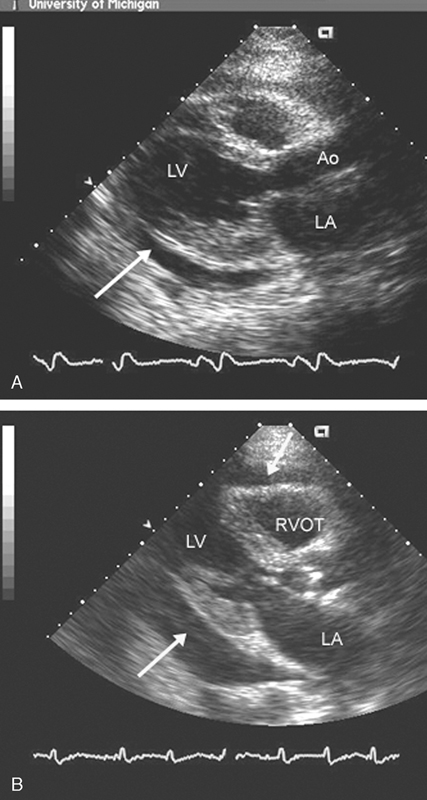

فحوصات تشخيصية لبعض امراض القلب والشرايين التاجية